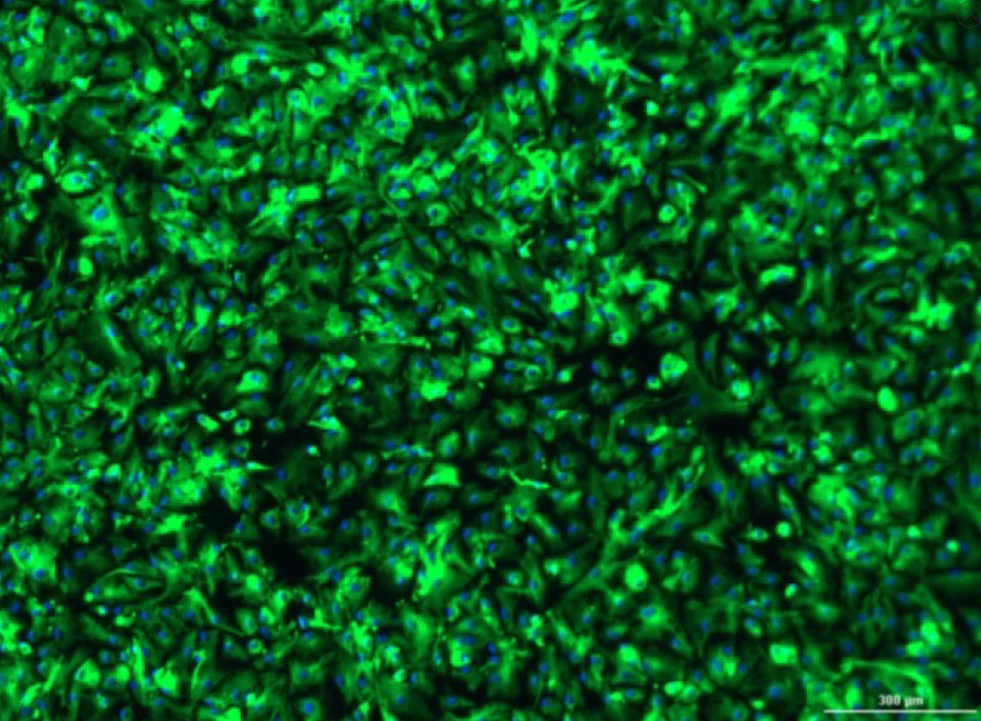

Human Glioblastoma Cancer-Associated Fibroblasts (CAFs): 1,000,000 Cells

Vitro Biopharma offers high-quality Human Glioblastoma Cancer-Associated Fibroblasts (CAFs) intended for in-vitro use in research applications only. These specialized cells serve as invaluable tools across multiple research areas. Our Human CAFs are sourced from well-characterized donor samples and maintained under rigorous quality control to provide you with reliable and consistent results. We offer Human CAFs from multiple donors. Matched Human Fibroblasts are also available from select donors.

• Cryopreserved at a low passage

• High passage capabilities

• Expands in VitroPlusIII Low Serum, Complete Medium (Vitro Biopharma, Cat. No. PC00B1–optimized for high growth rates, reduced doubling times, healthy cells, and stability)

• Able to grow in low oxygen (1% - 5% O2)